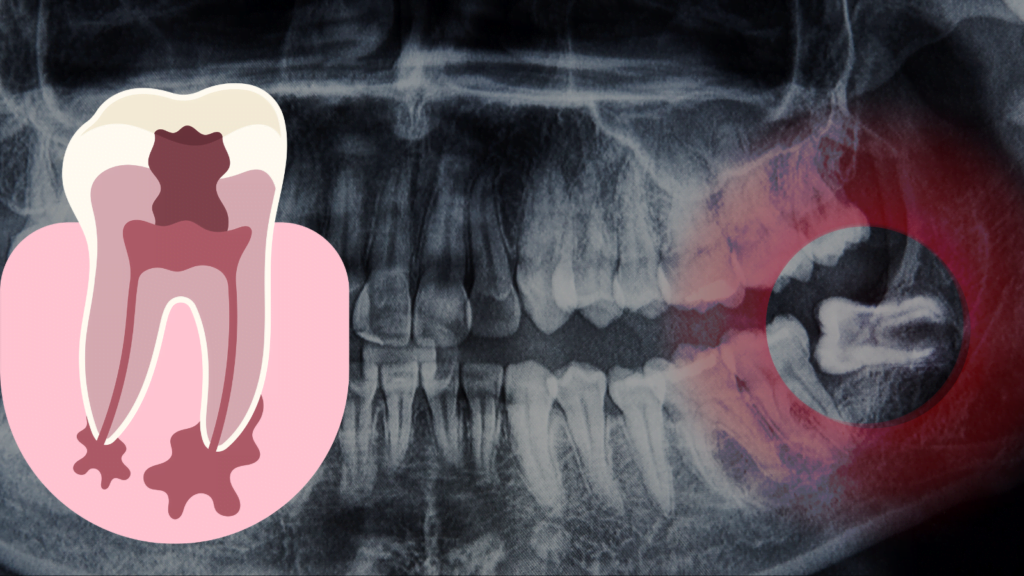

Are you looking for the best dental surgery clinic in Kolkata?At Apollo Dental Clinic, we combine expert care, advanced technology, and patient comfort to deliver outstanding results. Our goal is to help you feel confident before, during, and after your dental surgery. Why Choose Apollo Dental Clinic? Apollo Dental Clinic is one of the most […]